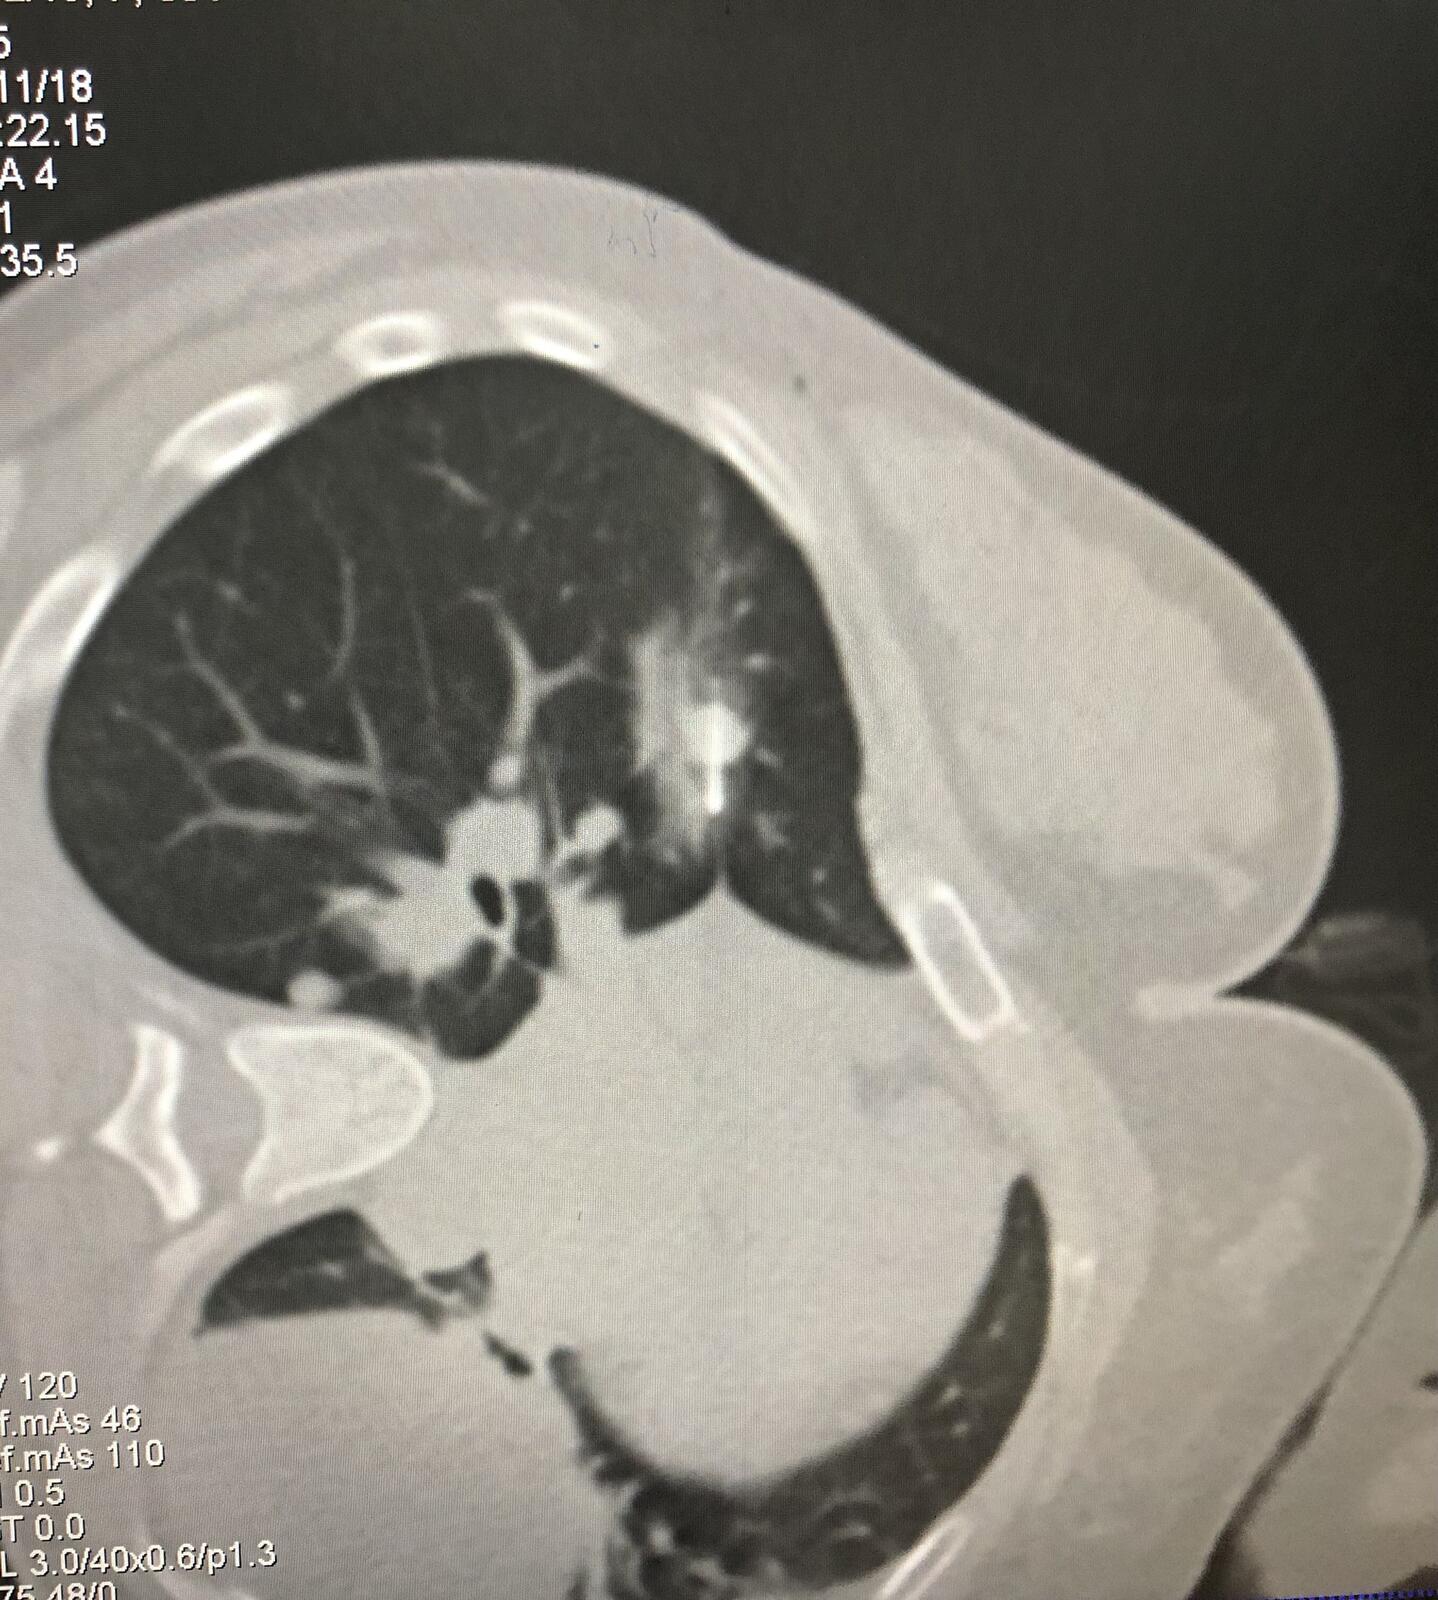

消融结束拔针后扫描提示消融范围完全覆盖病灶,提示病灶完全灭活。